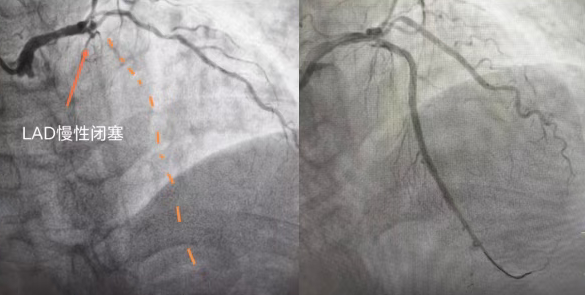

74 岁的陈阿姨(化名),数月来被反复胸痛折磨的寝食难安,稍一活动就胸口憋闷、刺痛难忍,休息后也难彻底缓解。辗转就医后,病情始终未获有效解决,最终在国文医院迎来转机:检查显示其心脏前降支近端钙化并完全闭塞,属于冠心病中难度极高的冠状动脉慢性完全闭塞病变(CTO),堪称冠脉介入治疗的 “最后堡垒”。

心脏正常运转依赖冠状动脉供血,前降支作为冠脉中供血范围最广、最关键的血管,负责心脏前壁、心尖等核心区域供血,一旦堵塞,极易引发大面积心肌缺血、急性心梗甚至猝死。这位老年女性所患的CTO病变,即冠脉完全闭塞超3个月,血管壁伴随大量坚硬钙化斑块,如同心脏“生命干道”被石块堵死,管壁脆硬。

此类病变凶险难治,一是钙化严重,普通导丝难以穿透;二是老年血管弹性差、易扭曲,术中易出现穿孔、夹层;三是闭塞时间长,血管走形难判断,对专家经验和技术要求极高。

手术由北京专家全程主导,操作精准细致,成功打通闭塞前降支,彻底解决老人心肌缺血问题。术后第二天,老人精神明显好转,可下地活动,家属对专家技术与医院服务充满感激。